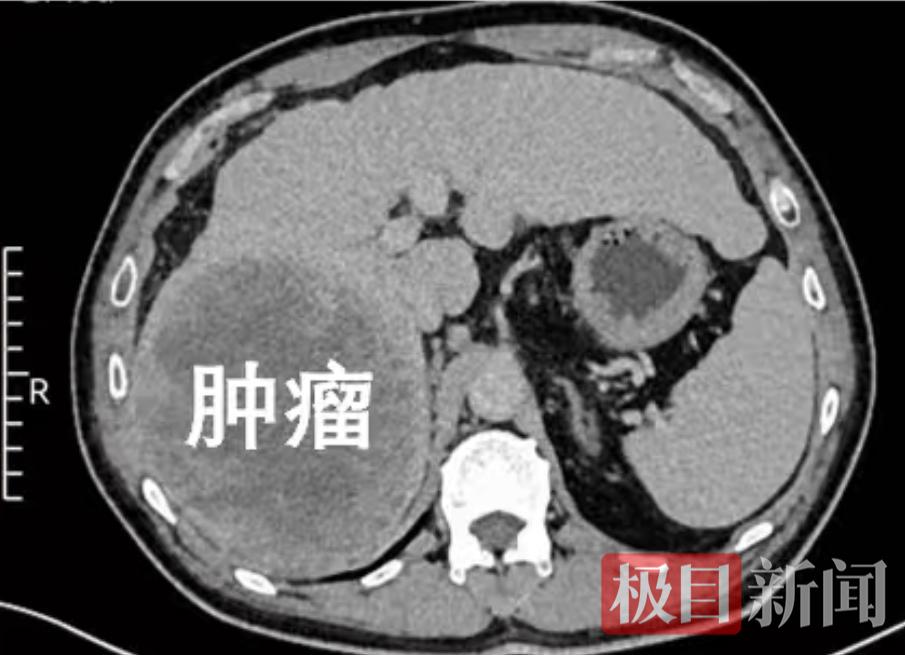

今年以来,吴先生频繁感到肝脏不适,到武汉市第六医院就医检查,影像报告显示:肝右叶长有一个直径达14厘米的原发性肿瘤。万幸的是,肿瘤仅局限于肝脏右半部分,未发生全身扩散,且吴先生肝功能状况良好,为手术治疗争取到了宝贵机会。

患者肝脏上的巨型肿瘤。